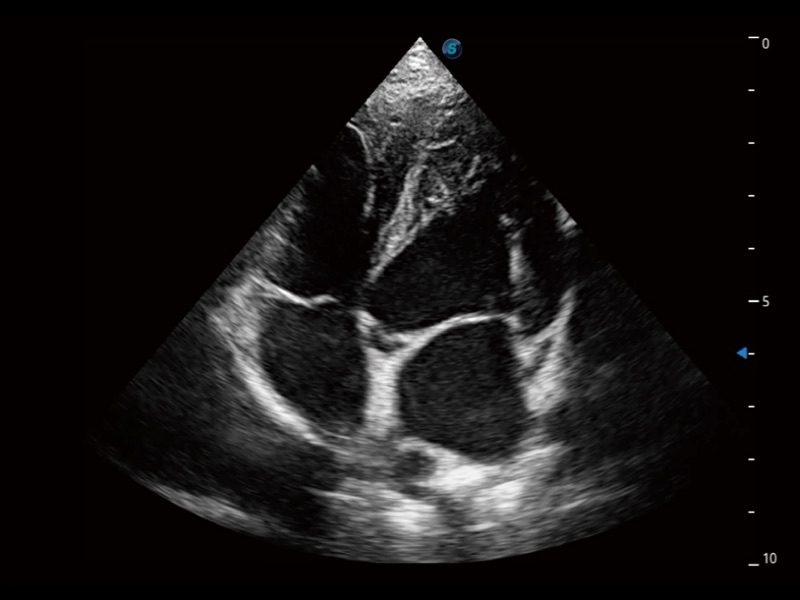

通過360度任意調(diào)節(jié)3條M型取樣線,在同一心動周期上觀察心臟不同位置的運動曲線,得到準確的心功能測量數(shù)據(jù),有效評估心肌運動及左心室功能。

實時用顏色表示心肌組織運動,觀察和定量組織的運動情況,對快速檢測與評估心肌的灌注和活性、電傳導(dǎo)及心肌收縮和舒張功能等均能提供重要的診斷信息。